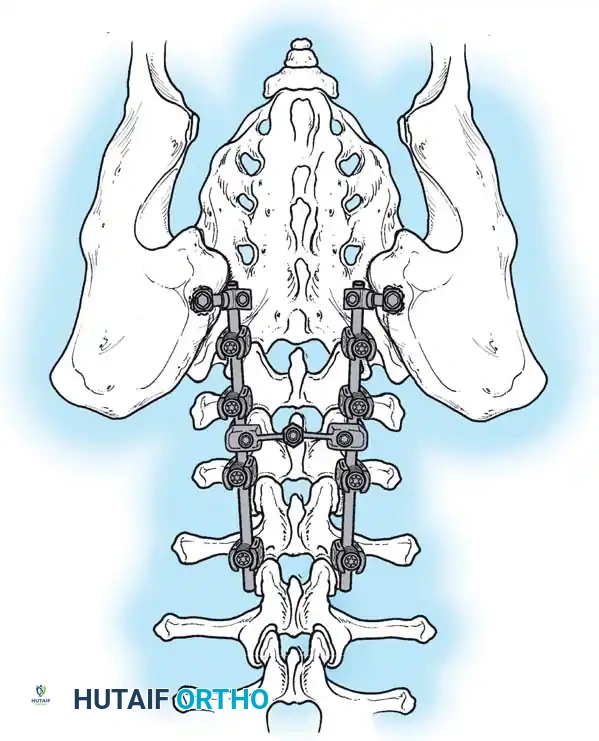

NEUROMUSCULAR SCOLIOSIS Surgical Diagram

• A: Clinical presentation of pelvic obliquity.

• B: If the pelvic obliquity resolves with abduction or adduction of the hips, the primary cause is a pelvic-femoral muscle contracture (infra-pelvic).

• C: If the obliquity persists despite hip positioning, a fixed spinopelvic deformity exists, necessitating fusion to the pelvis.

Image

Surgical Warning: Failure to recognize and release severe hip contractures prior to or concurrent with spinal fusion will result in persistent seating imbalance and immense stress on the distal spinopelvic instrumentation, leading to catastrophic hardware failure.

* Including the Pelvis: Mandatory for nonambulators with fixed spinopelvic obliquity. If bending or traction films reveal more than 10 to 15 degrees of L4 or L5 tilt relative to the interiliac crest line, the fusion must extend to the pelvis.